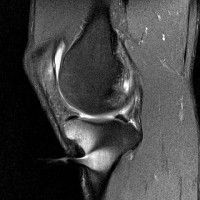

무릎 mri 간단히 봐주실 수 있으시나요 ㅠㅠ

안녕하세요 8년전 십자인대 수술하고 최근 무리한 운동에 무릎 불편감이 생겨서

mri 찍었습니다.

진단결과는 첫 찍은 병원에서 활액막염 이라는 진단을 받았습니다. 혹시 봐주실 수 있으실까요?

진단결과가 달라 혼란스럽습니다 ㅠㅠ

• 안녕하세요. 강성주 의사입니다.

올라온 MRI가 단편적이라서 정확한 진단에 어려움이 있지만 십자인대에는 큰 이상이 있지는 않은것 같으며, 무릎관절내 물이 있는 것으로 보아 활액막염의 진단이 맞을 것 같습니다.

하지만 단편적인 영상이기 때문에 촬영병원에서 정확한 판독지 등을 받으시는 것이 좋겠습니다.